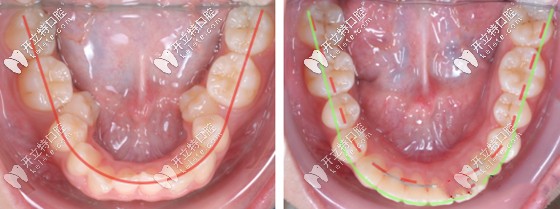

牙齒擴(kuò)弓矯正前后效果對(duì)比圖